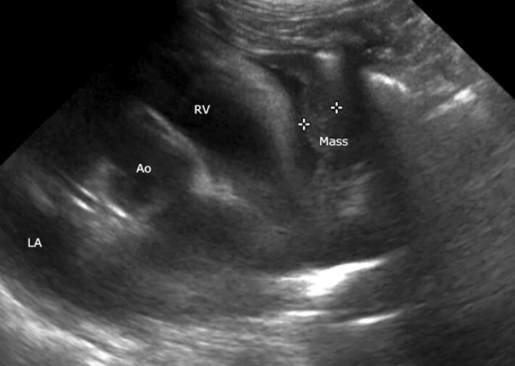

3살짜리 고양이의 심장 종양

심낭에서 발생한 육종에 대한 보고이다.

초음파 영상을 봤을때 나라면 어떻게 했을까? 를 고민해 봐야 한다.

나라면 아마도 심낭막염이나 흉막폐렴에 의한 장측 흉막 비후 정도를 우선하여 고려했을것이고

그래서 일차적으로 면역치료하고 강한 항생제 치료를 권했을것 같다.

당연히 치료반응이 없으면 수술을 통해 심낭절제술을 하면서 검체를 조직검사 보내보자고 했을듯,